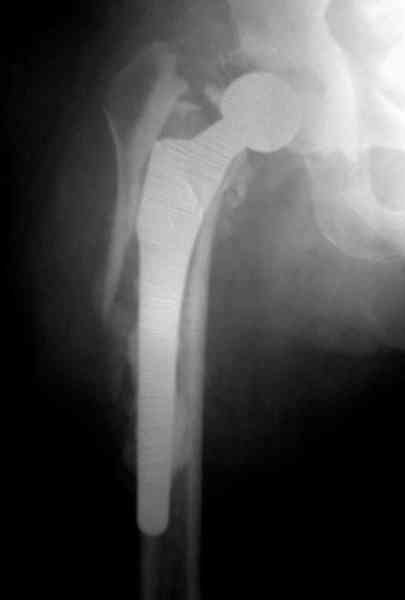

Представляю вашему вниманию снимки (прошу прошения за качество снимков) больной 48 лет с ревматоидным артритом, которой был сделан тотальный эндопротез справа,

контрольный снимок сделали только на 21день после операции (№1) и с интервалом 5 дней второй снимок (№2)

Судя по всему, произошел раскол наружной стенки бедра и ножка находится вне костного канала. В таком случае

решение одно - удаление ножки и установка новой в расчете на дистальную фиксацию. Конктреную модель подсказать тяжело из-за низкого качества Р-грамм.